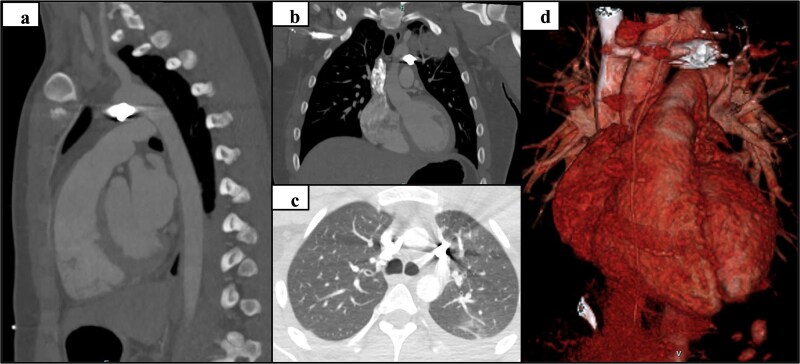

本病例研究报告了一名17岁的男性,在左上臂受枪伤后接受了机器人辅助的异物取出术,该枪伤导致子弹穿过胸壁直接停在主动脉肺窗处的纵隔。异物靠近大血管给术前成像和手术计划带来了挑战,因此成为这个独特病例的焦点。最终,机器人辅助取出子弹的手术成功了,没有损坏周围的结构。到目前为止,还没有关于机器人在这个解剖部位进行异物清除的研究报道。

This case study reports on a 17-year-old male that underwent robotic assisted foreign body removal after sustaining a gunshot wound to the left upper arm that resulted in the bullet traversing through the chest wall to stop directly in the mediastinum at the aortopulmonary window. The proximity of the foreign body to the great vessels introduced challenges for preoperative imaging and surgical planning, thus becoming the focus of this unique case. Ultimately, the robotic-assisted removal of the bullet was successful without damage to the surrounding structures. To date, no known study has reported on robotic foreign body removal at this anatomic location.